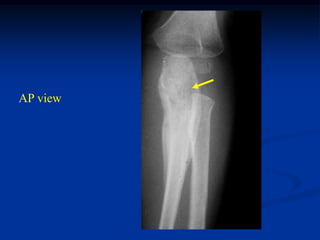

Case #1097

14 year male with

adamantinoma distal

tibia and fibula

Coronal T-1 MRI